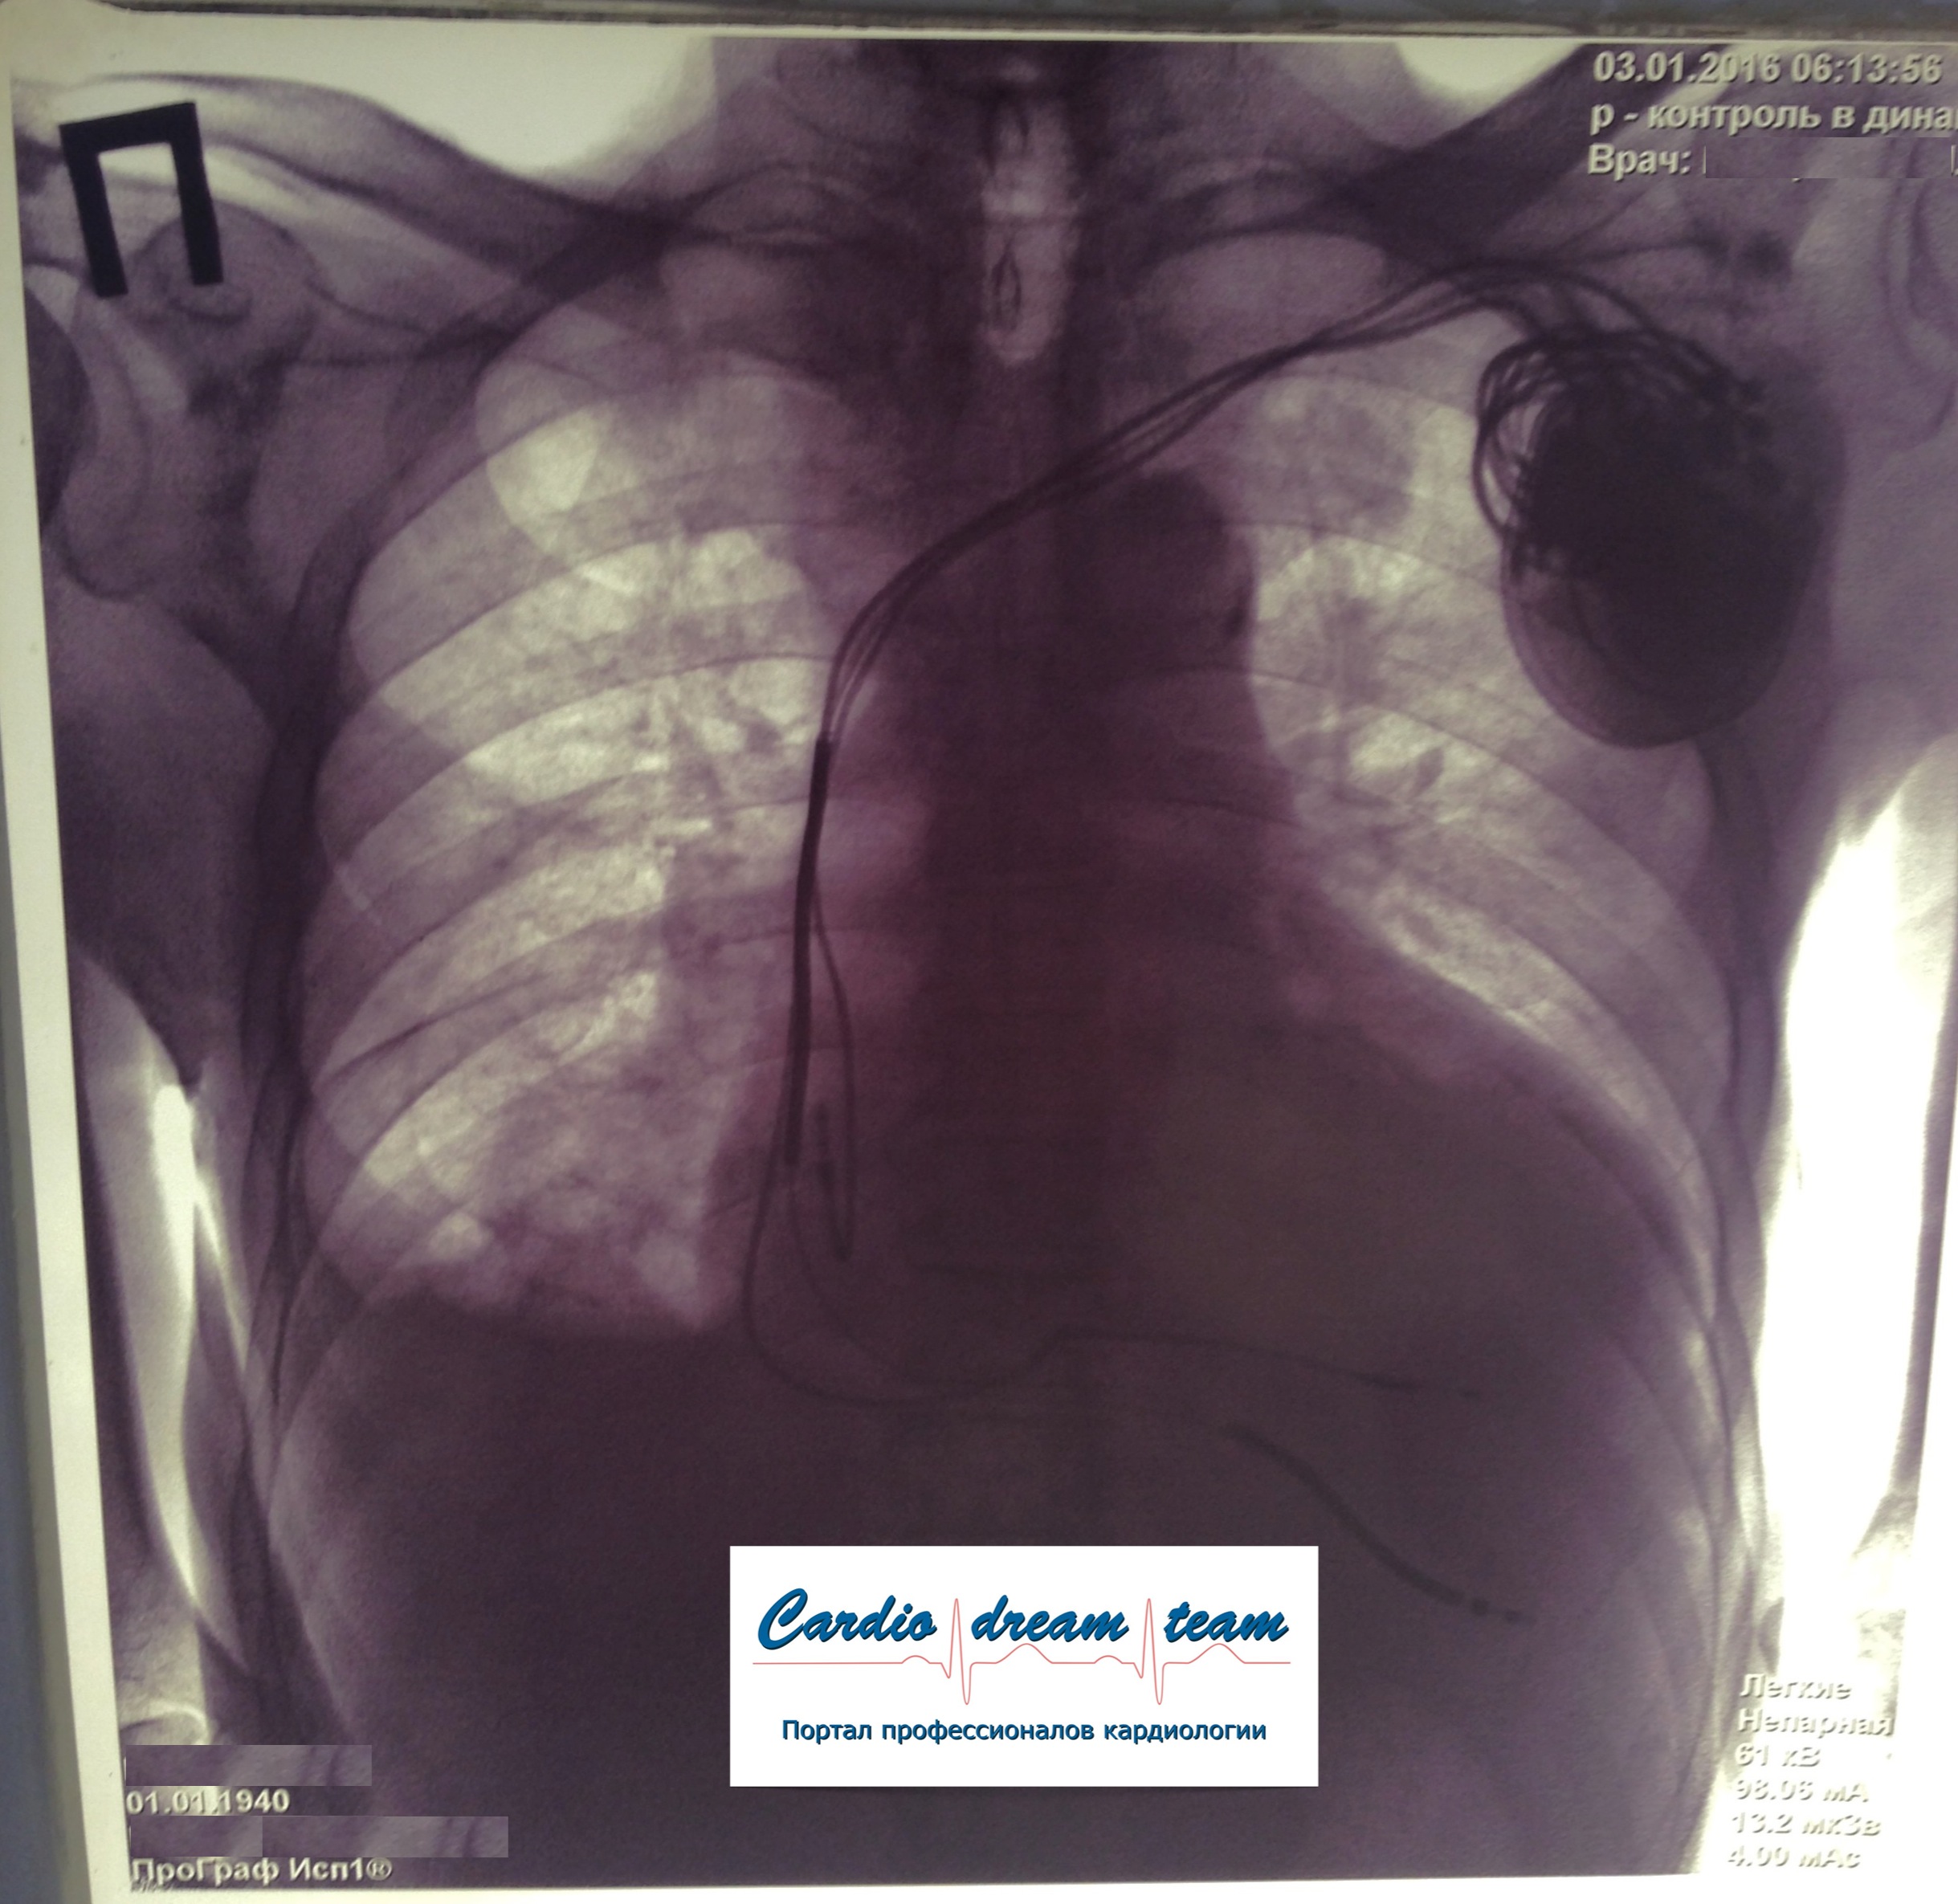

ИКД + ЭКС DDD. Когда всё на месте и всё работает.

2.jpg

2.jpg [ 800.72 KiB | Просмотров: 16796 ]